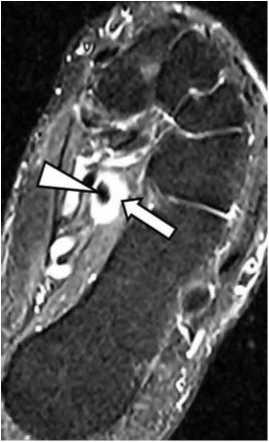

Рис. 4. Дислокация сухожилия длинного сгибателя большого пальца стопы.

На PD FSE, томограмме в аксиальной проекции определяется пустая костная борозда сухожилия длинною сгибателя большого пальца (треугольная стрелка), сухожилие смещено кзади (обычная стрелка).